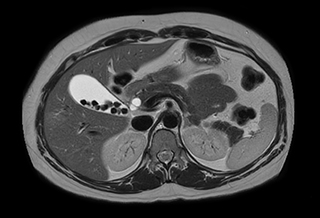

Excellent image quality is obtained in this dynamic scan., C-SENSE factor 5.4, scan time is 1:20 min, voxel size is 0.8 x 0.8 x 1.6 mm, Ingenia Ambition, 1.5T.

Cor 3D T2

Ascites can be hard to image, but excellent result is obtained with Ingenia Ambition. This high resolution image demonstrates the high quality that can be obtained with VitalEye and the patient just breathing normally. The acquisition time is fast thanks to the accuracy of the respiratory gating with VitalEye** and it also saves the time needed to put a respiratory belt on the patient.

3D T2 with VitalEye